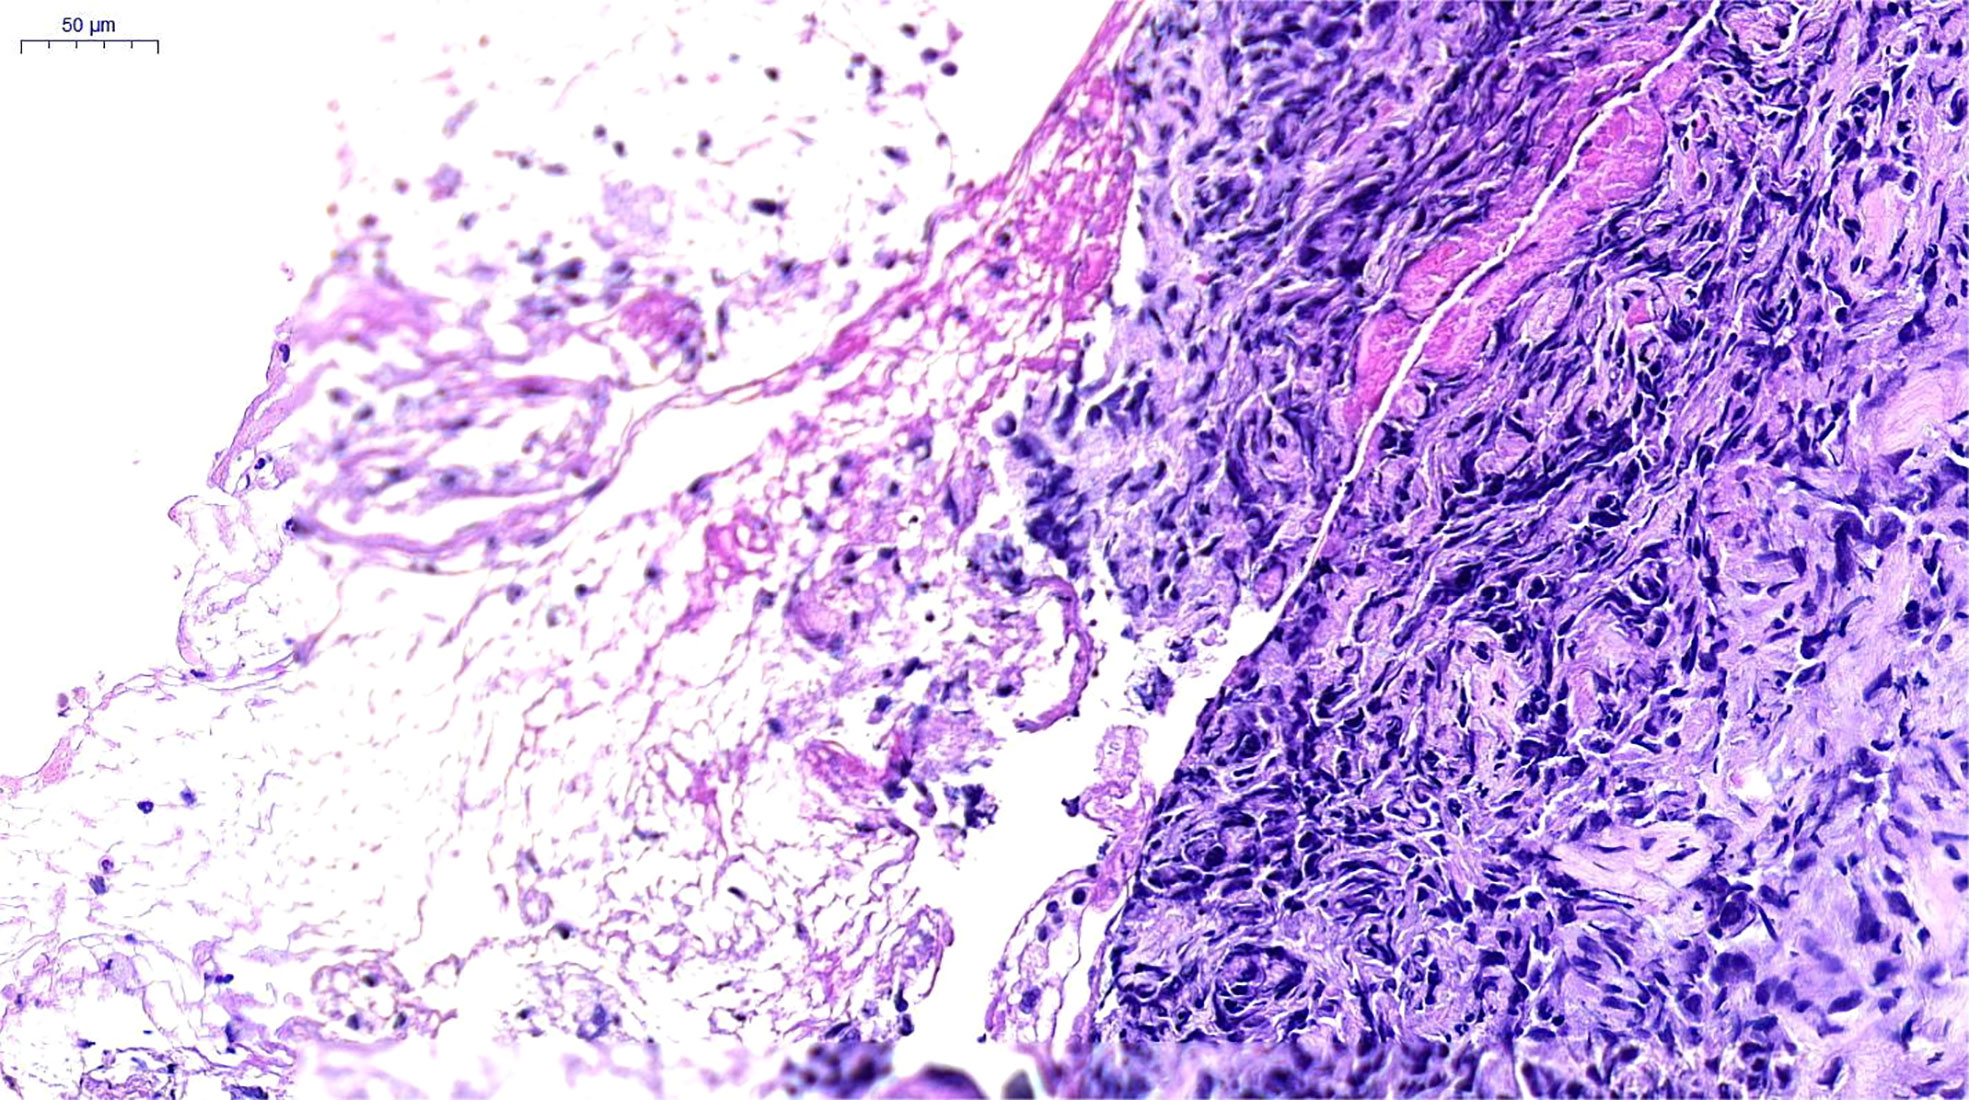

A 66-year-old female, with a history of Parkinson’s disease and hypertension, suffered from cough, expectoration, hemoptysis, and high fever on June 6, 2021. A chest computerized tomography (CT) revealed a space-occupying lesion in the lower lobe of the right lung. The quinolone antibiotic moxifloxacin was administered as an empirical treatment for community-acquired pneumonia, but the condition did not improve. On June 16, 2021, bronchofibroscopy revealed hyperemic bronchial mucosa in the lower lobe of the right lung, edema, and the formation of new nodules organisms with massive necrosis on the surface. Bronchoalveolar lavage, brushing, and biopsy were performed under tracheoscopy. Suspicious carcinoma cells were found and Staphylococcus aureus was cultured in the lavage fluid. However, only a few heterosexual cells and a large number of purulent secretions were found in biopsy tissue. On June 21, she was hospitalized for high fever, cough, expectoration, and asthma. An enhanced CT scanning was performed, indicating malignant lesions in the right lower lobe of the lung with obstructive pneumonia and atelectasis, truncation of the proximal bronchus, invasion of the right pulmonary vein, and multiple ground-glass nodules in both lungs (Figure 1A). During her hospitalization, linezolid was given, combined with symptomatic treatments such as resolving phlegm and relieving airway spasm and asthma; however, the clinical symptoms did not improve. A second bronchofibroscopy was performed on July 1, 2021; the middle segment of the right lung was microscopically completely obstructed by neoplasm. The pathological findings of the biopsy tissue suggested poorly differentiated PSC (Figure 2). The immunohistochemical results were as follows: Calretinin (weakly +), Syn (−), Ber-EP4 (−), CgA (−), CK5/6 (weakly +), NapsinA (−), Ki-67 (70% +), TTF-1 (−), P40 (−), P63 (−), CD31 (−), CK (AE1/AE3) (+), EMA (weakly +), LCA (−), Vimentin (+). In addition, the tumor stage was T4N0M0. Real-time fluorescence-based quantitative PCR showed no mutations in EGFR, ALK, ROS1, RET, NRAS, and PIK3CA, but mutations in G12A/V/R/C and G13 of KRAS exon 2.

FIGURE 2

Figure 2 Pathological Findings. Poorly differentiated carcinoma, consistent with pulmonary sarcomatoid carcinoma. H&E×200, hematoxylin and eosin stain.